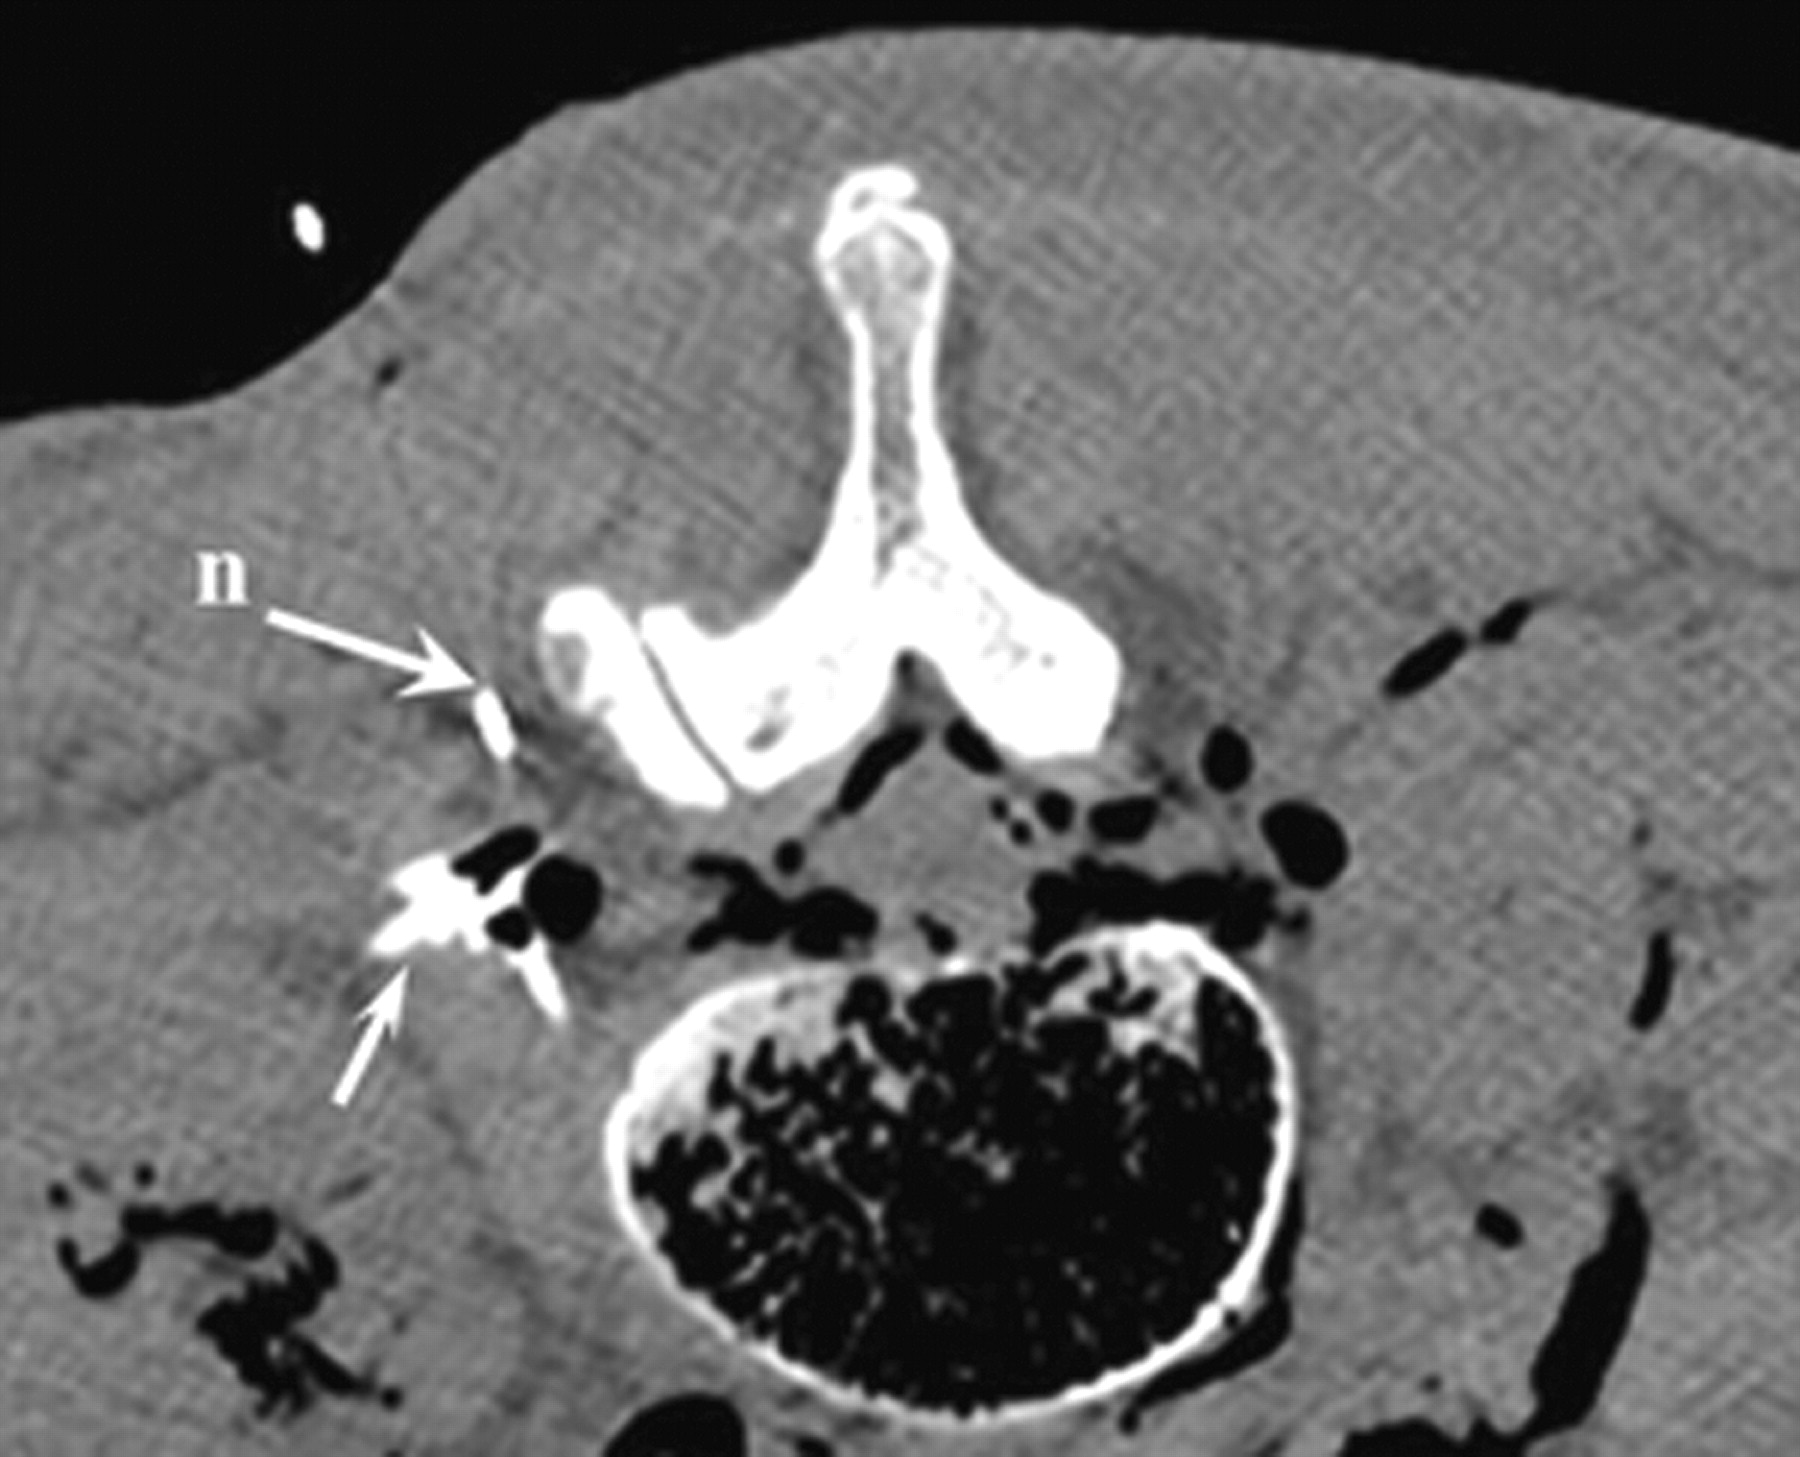

Corresponding axial CT scan at levels L2-L3, demonstrating the needle and contrast enhancement in the pararadicular area (arrow).